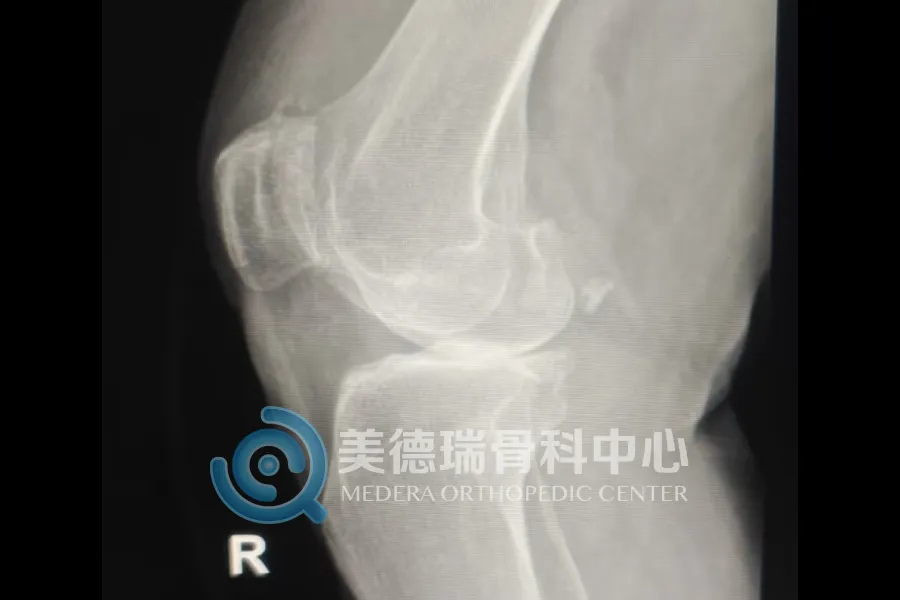

这些患者普遍有一个共同特点,就是病程长、疼痛重、走路越来越困难,日常生活已经受到明显影响。随着关节持续退变,不少患者逐渐出现膝关节变形、行走困难,上下楼和日常活动都受到影响。

重度膝关节骨关节炎发展到后期,关节磨损明显,疼痛会反复加重,腿形和力线也会随之改变。到了这个阶段,全膝关节表面置换术是较为成熟、有效的治疗方式。手术的目标也很明确,就是减轻疼痛,纠正畸形,恢复负重和行走能力。

近期接受治疗的一位68岁患者就是一个典型的例子。双膝疼痛已持续8年,近1个月明显加重,同时合并高血压和糖尿病。入院检查显示,其膝关节退变已较为严重,关节间隙明显变窄,力线也已发生改变,日常行走受到明显影响。经过术前评估和围手术期准备后,美德瑞骨科中心为其实施了全膝关节置换术。术后复查显示,患肢力线得到纠正;从术后站立和行走情况看,患者恢复平稳,已具备早期下地活动条件。